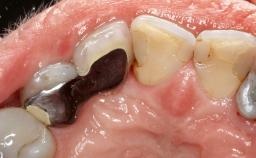

Resective Surgical Treatment of Peri-Implantitis Including Implantoplasty

In this case, Myroslav Solonko, Ignacio Sanz Sánchez and Mariano Sanz present a treatment that aims to eliminate exposed implant threads by modifying the implant surface, converting a moderately-rough surface into a smooth surface.

A 63-year-old male patient was referred to the post-graduate periodontal clinic of the Complutense University of Madrid for the treatment of peri-implantitis. According to the patient’s record, all his maxillary teeth had been extracted ten years previously due to severe periodontitis, and a full-mouth implant-supported restoration on eight implants was placed. No supportive periodontal therapy was provided apart from occasional check-ups by the restorative dentist.